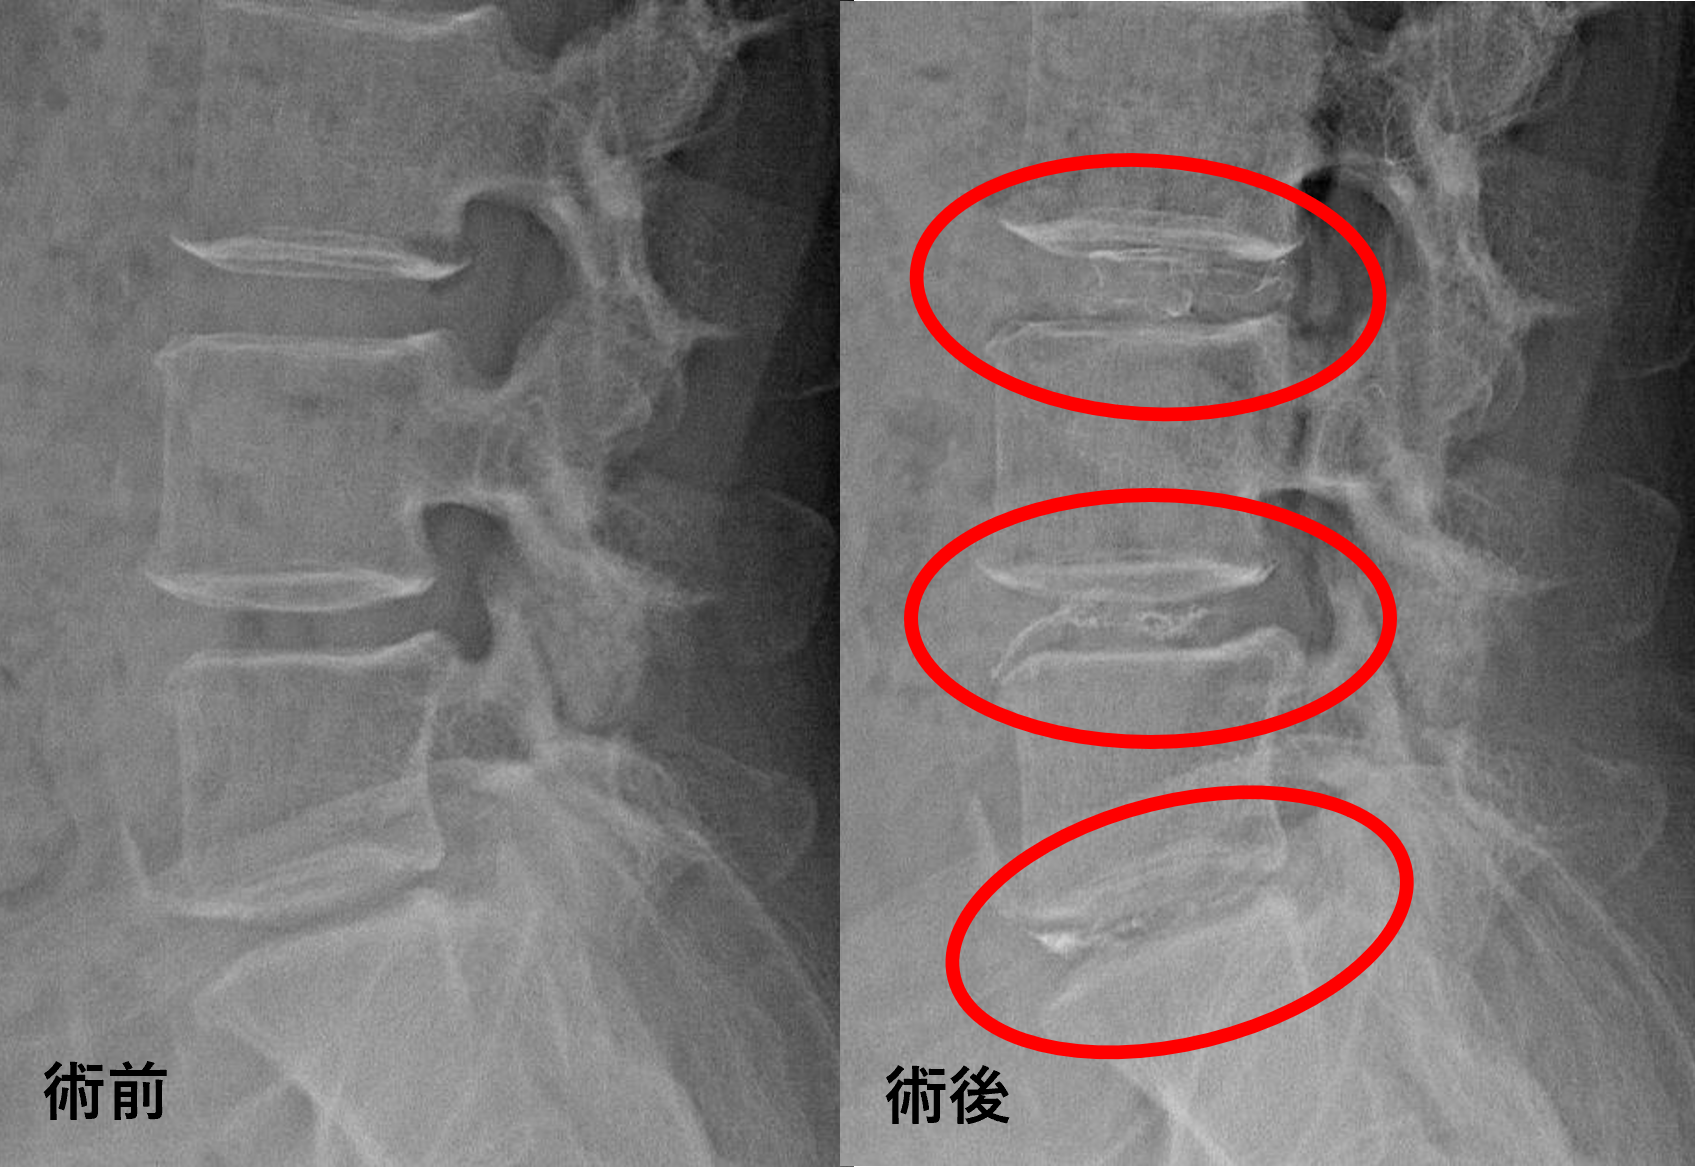

画像及び所見について

- L3/4、4/5、5/s – 椎間板変性、膨隆、椎間孔狭窄

以上のことが画像上認められました。

L3/4、4/5、5/sの椎間板所見による脊柱管の圧排が、症状の原因の可能性が高い。

患者様と相談の元、L3/4、4/5、5/sにセルゲル法を施行